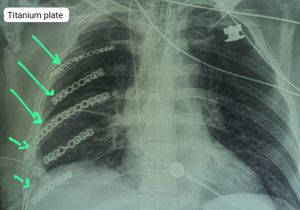

सड़क दुर्घटना में बुजुर्ग की पसली हो गई थी चकनाचूर, टाइटेनियम प्लेट की नयी पसली बनाकर बचाई जान

15 Sep, 2023 12:52 PM IST | SAMWADINDIA.INरायपुर आठ दिन पहले 63 वर्षीय बुजुर्ग जो राजिम के रहने वाले हैं एवं पेशे से...